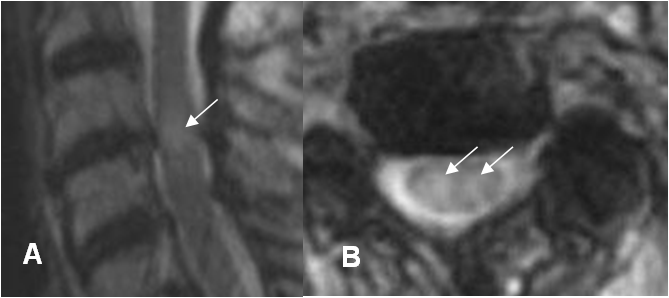

Fig 177 A. Edema medular.

A: RM sagital y B: RM axial en T2. Edema de la medula espinal, con área hiperintensa.

Fig 177 B. Edema medular.

A: TAC reconstrucción lateral y B: RM sagital en GE. Anterolistesis GI de C5, sobre C6 y cambios degenerativos con osteofitos posteriores, que comprimen el saco dural.

C: RM sagital en T2 y D: RM sagital en STIR. Además de la compresión del saco dural, se aprecia hiperintensidad medular entre C5 y C7, por contusión (Flechas delgadas). Existe pequeña colección prevertebral y edema en los tejidos blandos posteriores. (Flechas gruesas).